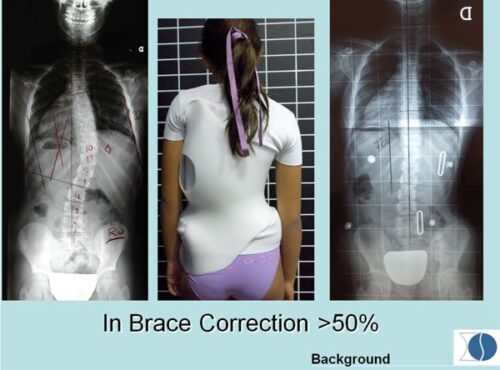

نجاح الحزام الطبي لعلاج اعوجاج العمود الفقري عند المراهقين لا يعتمد على ارتدائه فقط، بل على تفاصيل دقيقة مثل تصحيح الأنحناء وسرعة هذا التصحيح. متابعة الأهل مع الطبيب، الالتزام بعدد ساعات الارتداء، واستخدام الحزام المصمم خصيصًا لكل طفل، جميعها عوامل تزيد من فعالية العلاج وتمنح الطفل فرصة أفضل لنمو ظهر مستقيم وحياة طبيعية.

التطور الكبير في تصميم الأحزمة الطبية جعل علاج اعوجاج العمود الفقري عند المراهقين أكثر نجاحًا وأقل إزعاجًا. باستخدام تقنيات التصوير الثلاثي الأبعاد والمحاكاة الرقمية، أصبح الحزام أكثر خفة وراحة، ويعطي نتائج أفضل في تصحيح الانحناء والتواء العمود الفقري.

امنح طفلك فرصة أفضل لمستقبل صحي مع حزام PioBrace المتطور من مركز الرواد. يتميز هذا الحزام بتقنيات تقويم متقدمة تضمن نسبة تصحيح عالية لاعوجاج العمود الفقري، مع اعتماد فريق طبي متخصص يراقب التقدم بشكل مستمر لضمان عدم تفاقم الانحناء مستقبلاً. اختروا مركز الرواد، حيث تلتقي الخبرة الطبية بأحدث الابتكارات، لنوفر لطفلكم علاجًا مخصصًا وآمنًا يعيد التوازن لجسمه بثقة واحترافية. صحتهم أمانة ونحن هنا لنحافظ عليها.

- فعالية مثبتة علميًا: يساعد الحزام في إيقاف تقدم الاعوجاج وتقليل الحاجة إلى التدخل الجراحي.